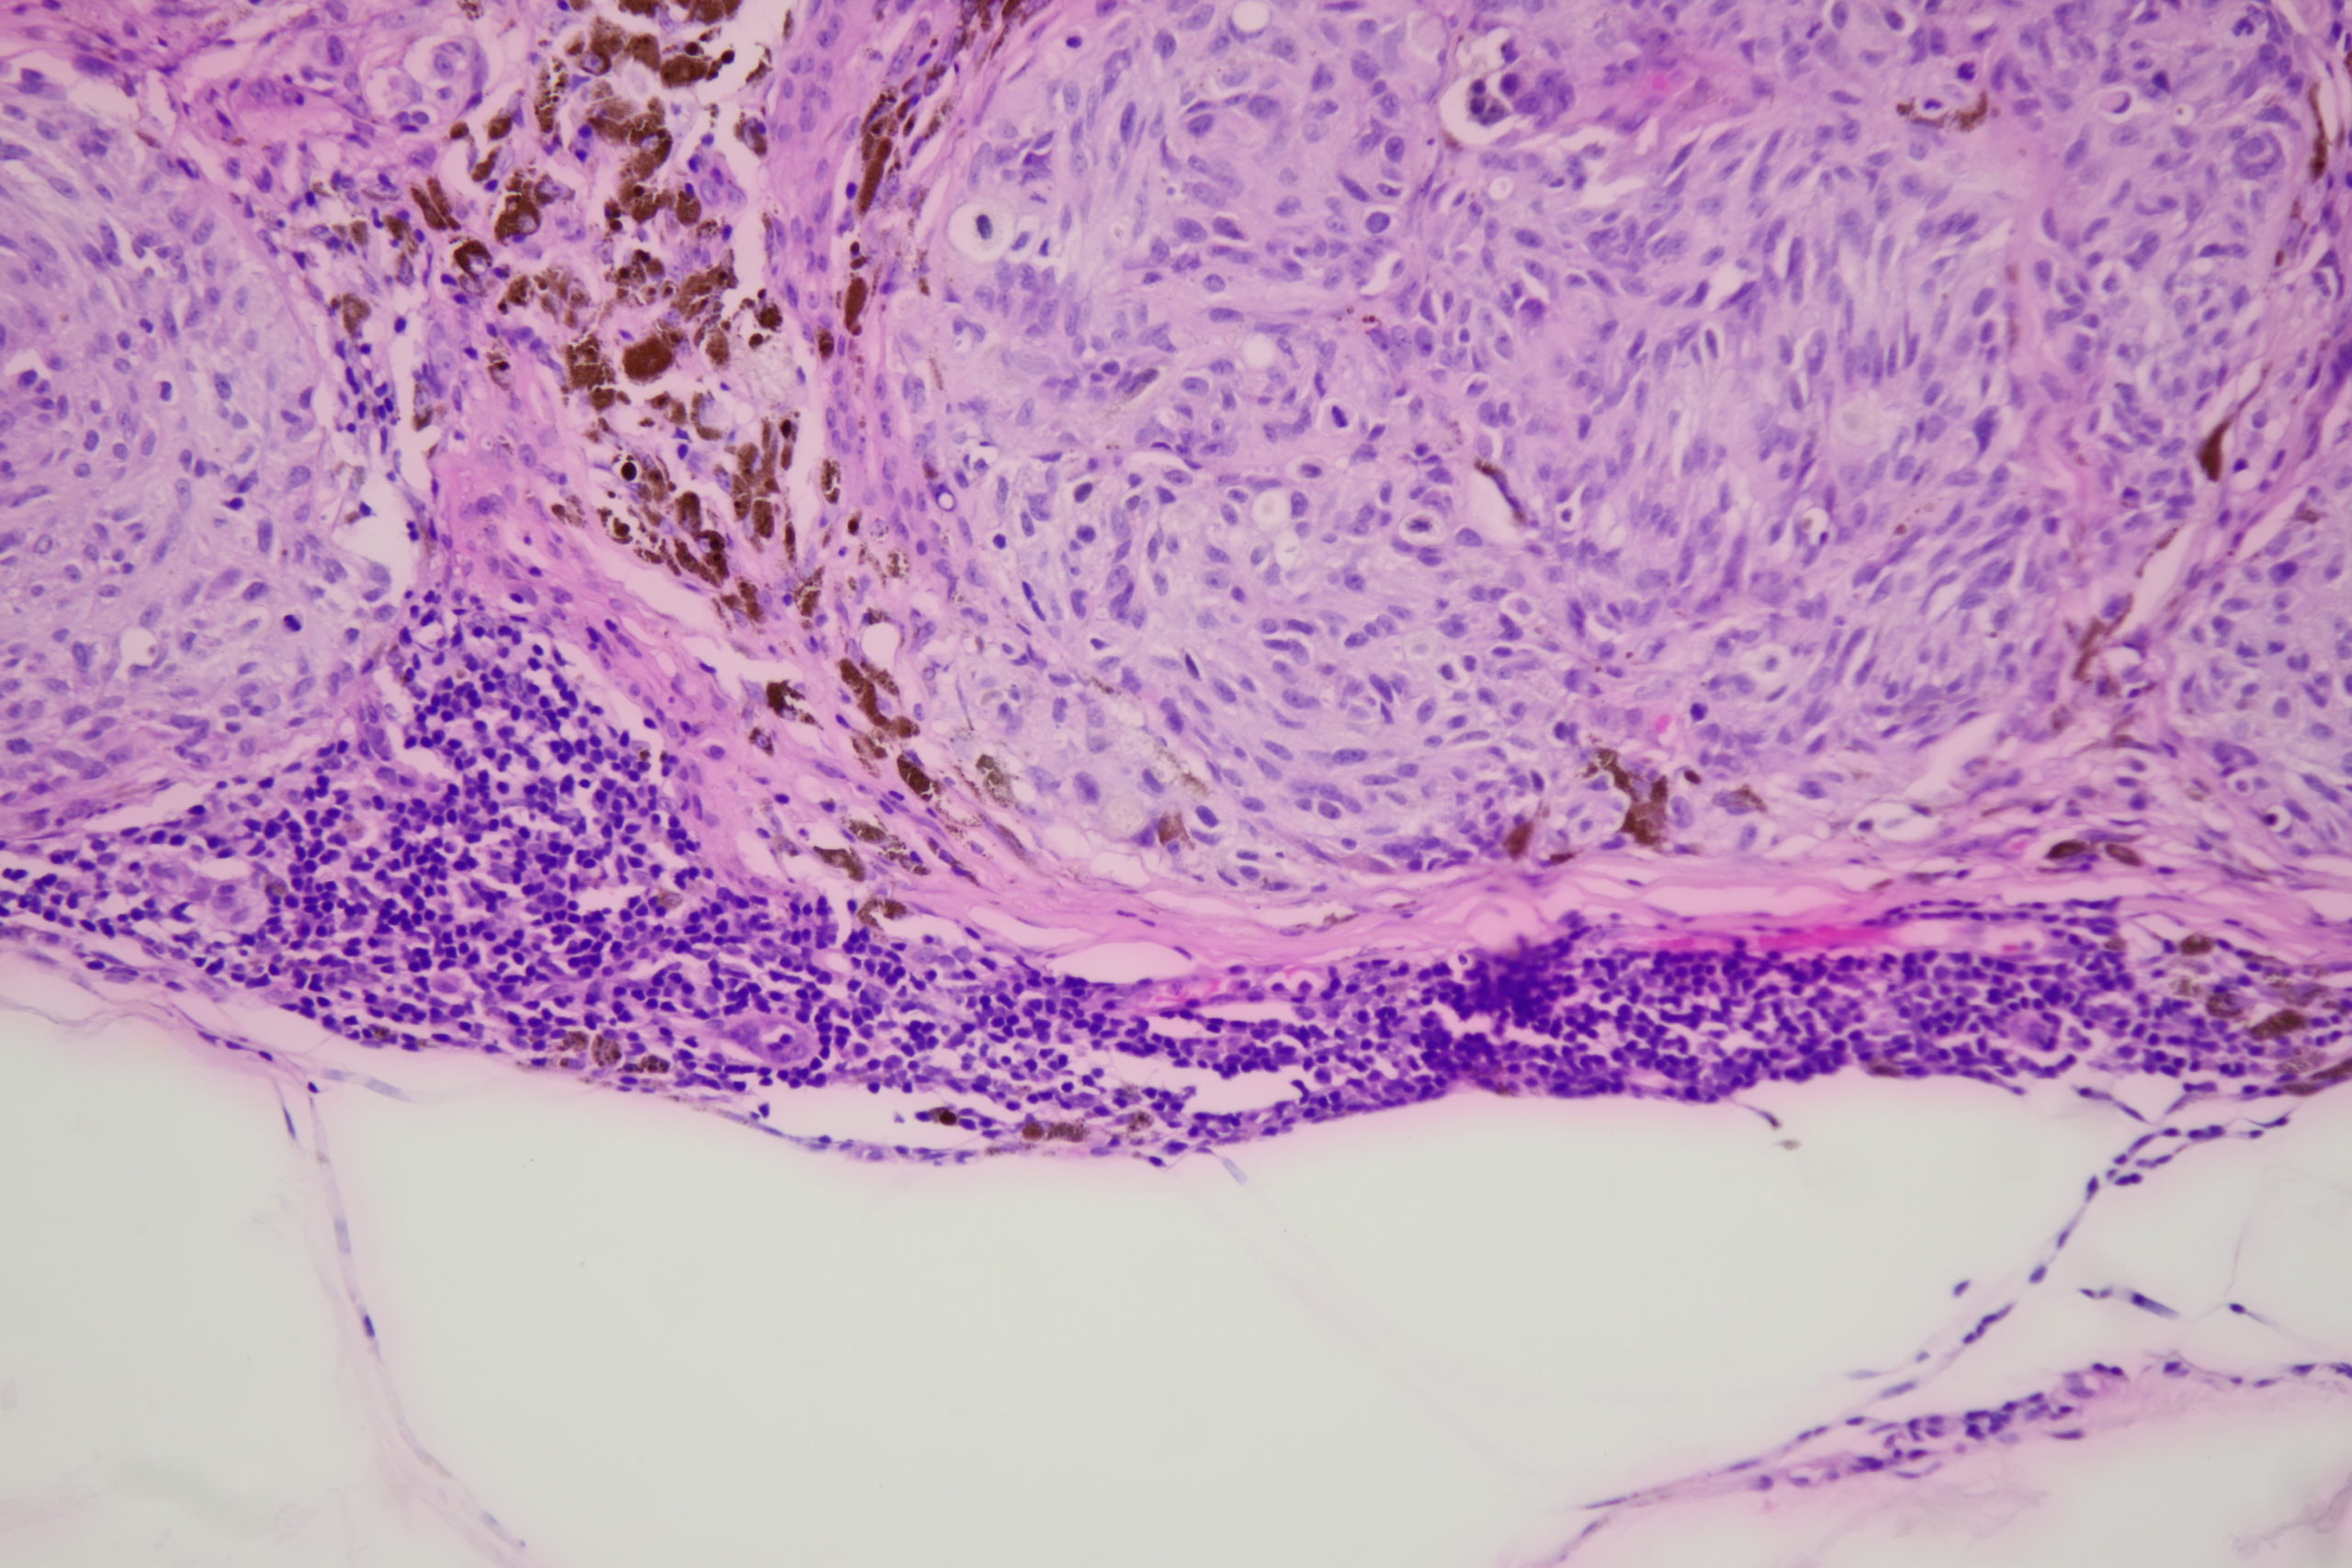

Image Number #3765 (Melanoma nodular)

Diagnosis: Melanoma nodular

Pigmented lesion upper back

This lesion was noted during a routine skin examination in an elderly patient on immunosuppressives for an autoimmune disease.

The lesion was a 0.55 mm thick Clark level 3 nodular melanoma.